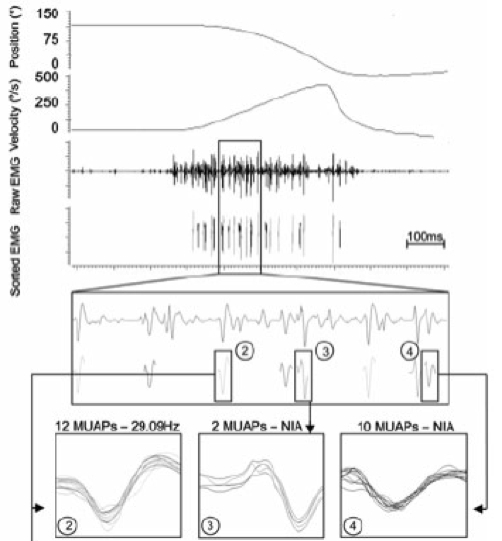

Research studies in my lab are directed at describing and understanding muscle contractile output (force or torque) in relation to neural activation and motor control of the muscle. We study these aspects in humans at a systems level with an integrated approach using minimally invasive techniques.